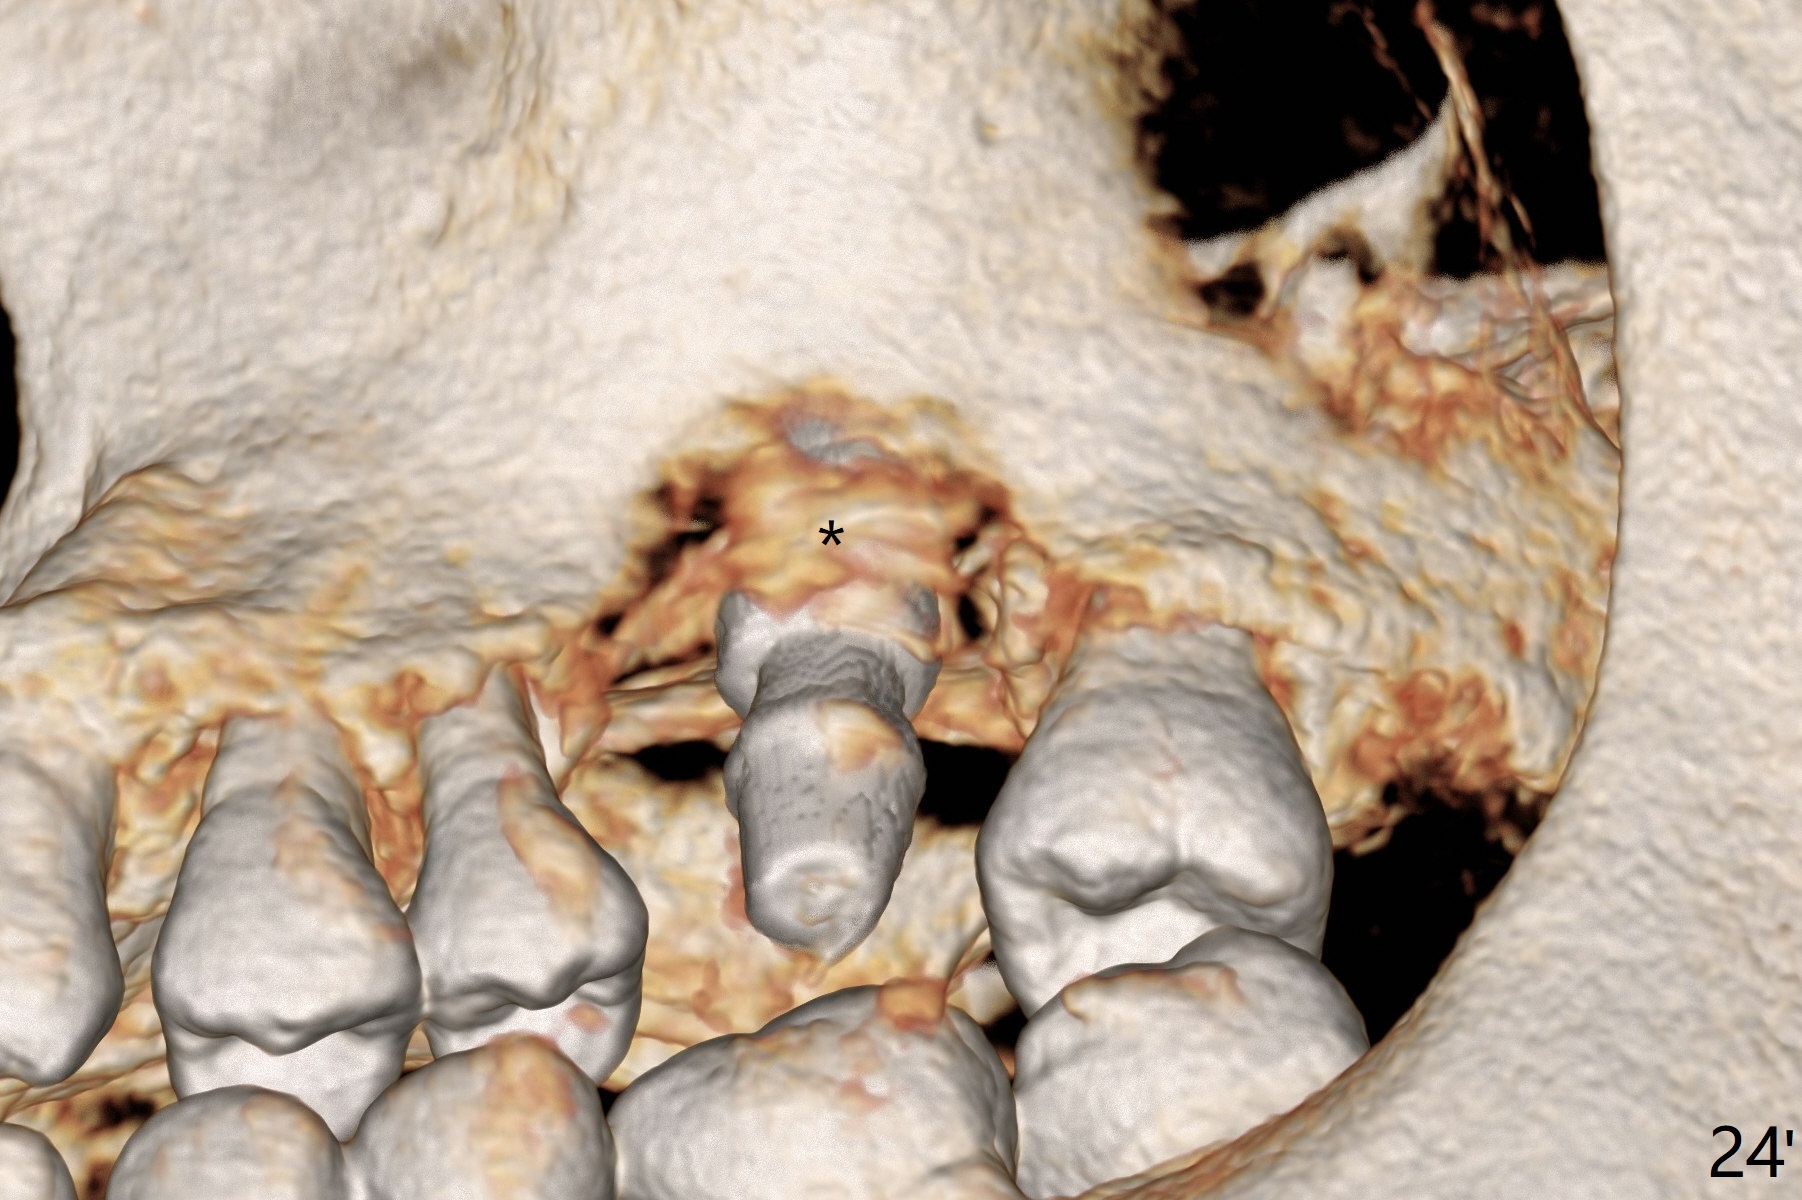

When the displaced tooth #14 (Fig.1) with palatal gingival recession (Fig.2) is extracted, the buccal plate is low, while the palatal one is lost.  Osteotomy is initiated in the bottom of the large socket with Marking Drill.  The bone turns bluish, suggesting thin bone (in fact less than 1 mm as well as low density).  Magic Sinus Lifter (Fig.3 *, Fig.4 blue area) is used for sinus lift (Fig.4 (red curved line: lifted sinus membrane; grey area: a portion of the lifted sinus floor), followed by insertion of a piece of PRF plug and Vanilla bone graft for sinus lift.  The osteotomy is enlarged lightly with 4.8 mm Magic Drill (compare black strips between Fig.4,5).  A 5x9 mm dummy implant (Fig.5 green) is dislodged into the sinus.  The lifted sinus membrane holds the implant in place.  The black thin strip in Fig.5 and black circle in Fig.6a (occlusal view) represents the osteotomy.  After increase in the osteotomy with Lindamann bur (Fig.6b red circle), the implant (Fig.6c green) is retrieved with endodontic forceps (Fig.6c two blue dots (beaks of the forceps); Fig.7,8).  With the enlarged osteotomy (Fig.6d), a 6x9 mm dummy implant is placed deep (Fig.9).  The definitive implant is 6.5x11 mm with insertion torque ~ 15 Ncm (Fig.10).  With placement of a healing screw and further placement of allograft (Fig.11 *), the socket is closed with PRF membrane and collagen plug (Fig.12).

There is a mushroom around the implant nearly 5 months postop/immediately before cementation (Fig.21).  The bone density around the implant is low (Fig.22-24' *).